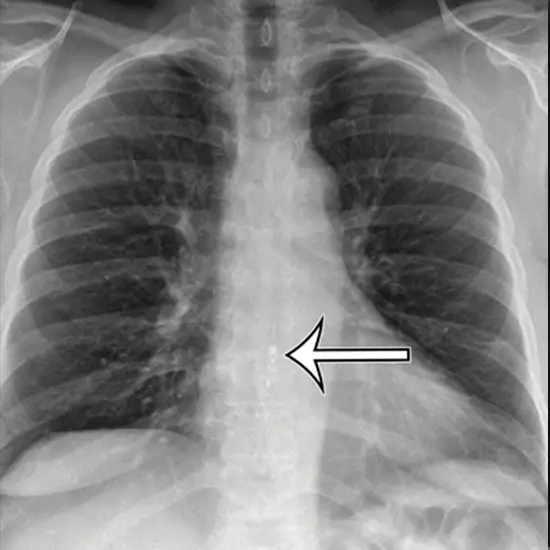

An X-ray of the Oesophageal Area A.P. (F. Body) identifies accidentally ingested external objects such as chicken or fish bones, buttons, marbles, screws, button batteries, and straight pins in children, as well as the location of swallowed fish bones, coins, fruit pits, straight pins, and dentures in adults, as well as a blockage caused by external objects in the upper gastrointestinal tract, which can lead to upper G.I. infections.